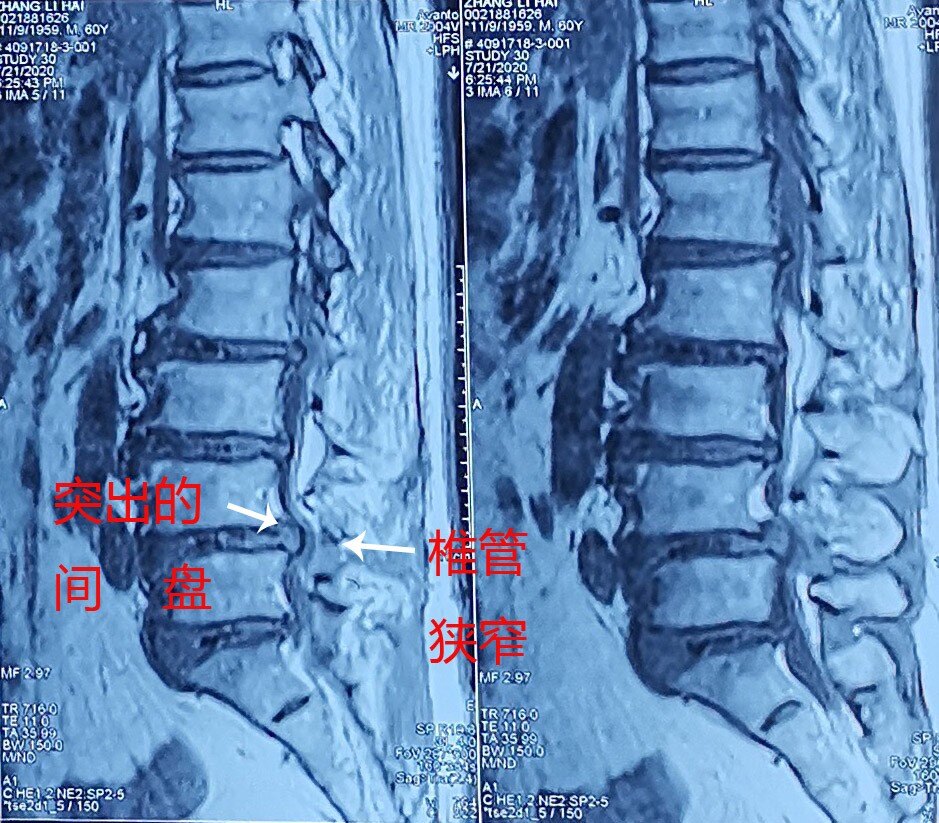

中医学典籍中无腰椎间盘突出症之名,根据该病的临床表现,可归于“腰痛”、“腰腿痛”、“痹症”等范畴。腰间盘相当于一个微动关节,是由透明软骨板、纤维环和髓核组成,分布在腰椎骨间。腰椎间盘退行性改变或外伤所致纤维环破裂,髓核从破裂处脱出,压迫腰椎神经,而出现腰腿放射性疼痛,也有是产后或是人流后感染受风导致的腰椎间盘突出的发生,所以医学界认为腰间盘突出属“腰腿痛,痹症”范畴。

腰椎间盘突出